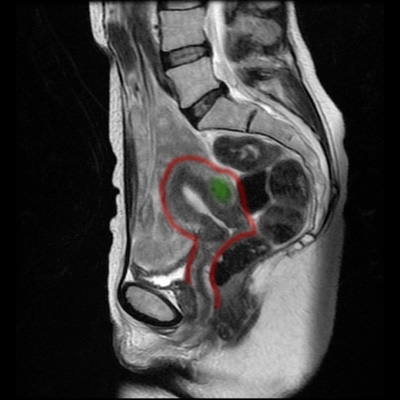

Studium przypadku 47-letniej pacjentki z kilkoma mięśniakami o średnicy do 5 cm.

Obrazy MRT 11 miesięcy po leczeniu metodą MRgFUS. Mięśniaki nie są już wykrywalne lub znacznie się obkurczyły. Trzy miesiące po zastosowaniu leczenia pacjentka nie miała już żadnych dolegliwości.